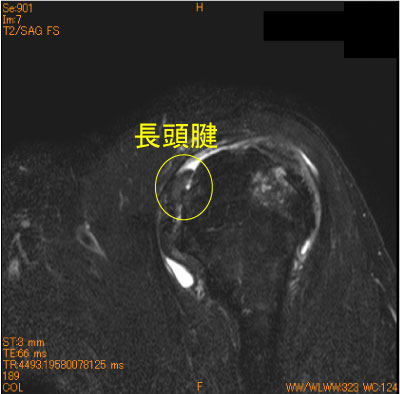

長頭腱脱臼-肩関節MRI-

70代男性、転倒後疼痛肩。

棘上筋腱、棘下筋腱の全層広範断裂に目を奪われ、長頭腱の脱臼を見逃してはならない。

必ず長頭腱の走行をcheckすること。

![]() Obl. Sag T2WI 脂肪抑制 |